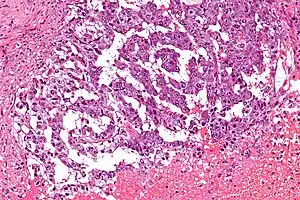

| Micrograph showing the yolk sac component of a mixed germ cell tumour. H&E stain. | |

EST can have a multitude of morphologic patterns including: reticular, endodermal sinus-like, microcystic, papillary, solid, glandular, alveolar, polyvesicular vitelline, enteric and hepatoid.

Histopathology of endodermal sinus tumor with Schiller–Duval bodies.

(a) papillary pattern combined with small tubopapillary endodermal sinus structure (Schiller–Duval body) in blue circle;

(b) marked tubulopapillary sinusoidal structure with central vascular core in longitudinal section (Schiller–Duval body);

(c,d) 400× g magnified image plus zoom of diagnostic round cystic Schiller–Duval body in a transverse section, with microcystic and papillary patterns around. The body has a central vessel surrounded by fibrous tissue, called the fibrovascular core, and it is surrounded by layers of the tumoral cells at the surface of that stalk. The structure is located in open cystic space also lined by tumoral cells. All those structures together are called a Schiller–Duval body and resemble primitive glomerulus. H&E stain.[5]

Schiller–Duval bodies on histology are pathognomonic and seen in the context of the endodermal sinus-like pattern. Rarely, it can be found in the vagina.[6][7]